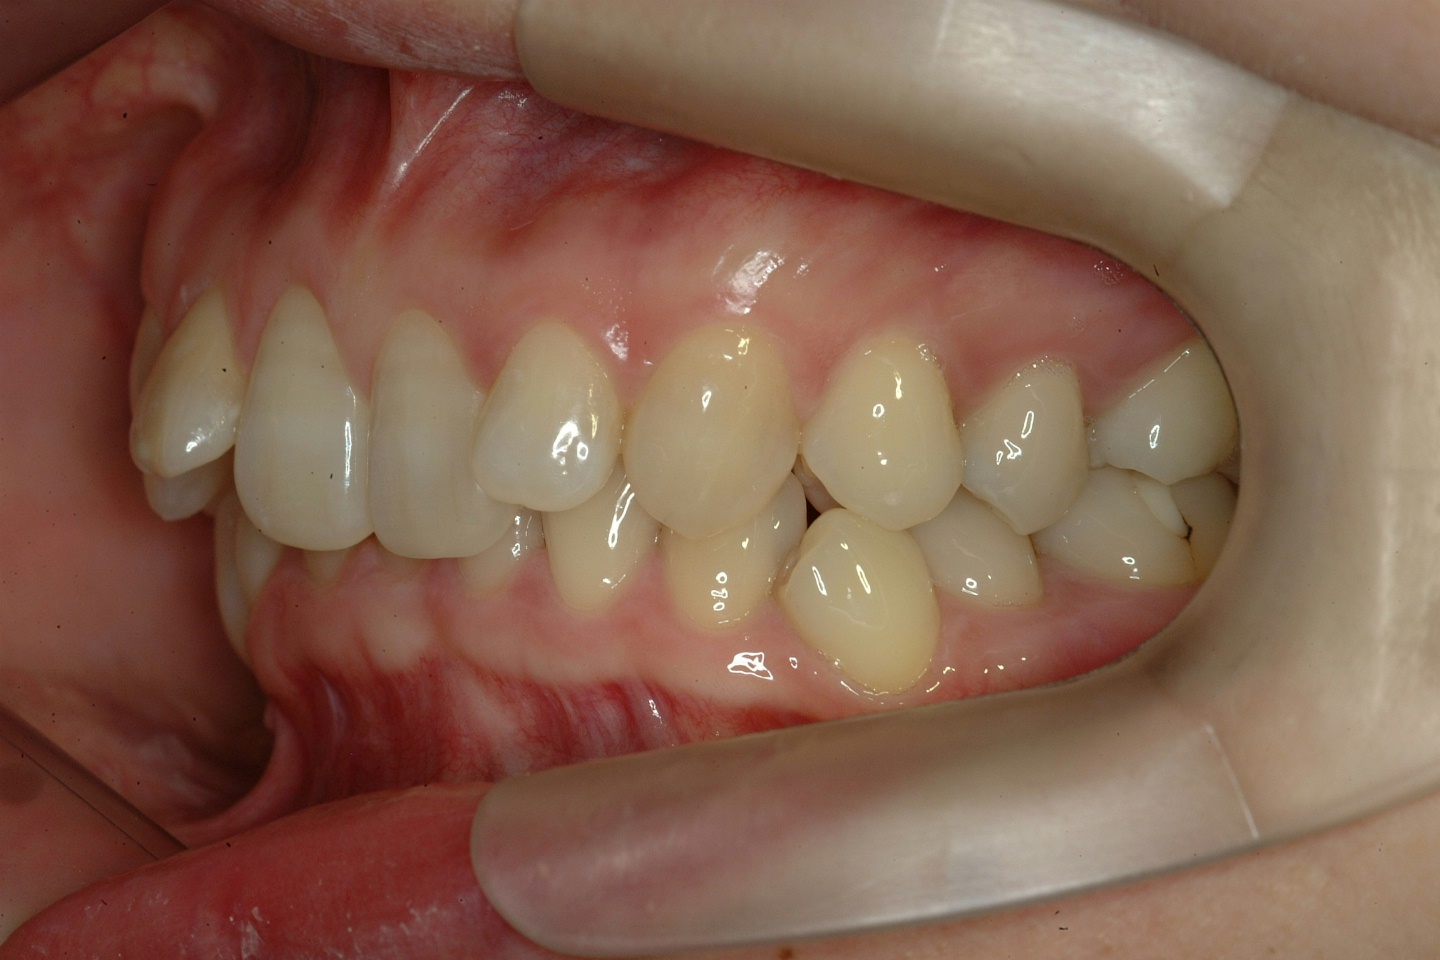

치료 전 사진입니다.